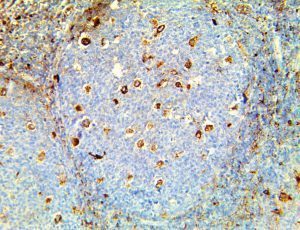

The first cytokines released are interleukin 1β (IL-1β) and tumor necrosis factor-α (TNF-α), which attract a variety of circulating white blood cells (WBCs) to the infection site, including neutrophils, monocytes, macrophages, and natural killer (NK) cells. This response, along with the antipathogenic chemicals released by these cells (i.e., complement), comprise the innate immune response. These cells directly attack the invading pathogen and also release additional cytokines, chief among them interleukin-1 and 6 (IL-6). IL-6 is essential for invoking the adaptive immune response, which calls T-cells, B-cells, and T helper (Th) cells to the infection site. IL-6 also stimulates further recruitment, proliferation and activation of macrophages.

It is the ICU physician who is most likely to witness one of the deadliest manifestations of the abnormal immunological response, the cytokine storm syndrome (CSS). This response is also referred to by some as the cytokine release syndrome (CRS). CSS is characterized by continuous activation and expansion of macrophage and lymphocyte populations, which secrete large amounts of cytokines, causing the cytokine storm. This massive cytokine release is akin to hemophagocytic lymphohistiocytosis (HLH) disease, a syndrome characterized by initial unchecked and persistent activation of cytotoxic T lymphocytes and NK cells.